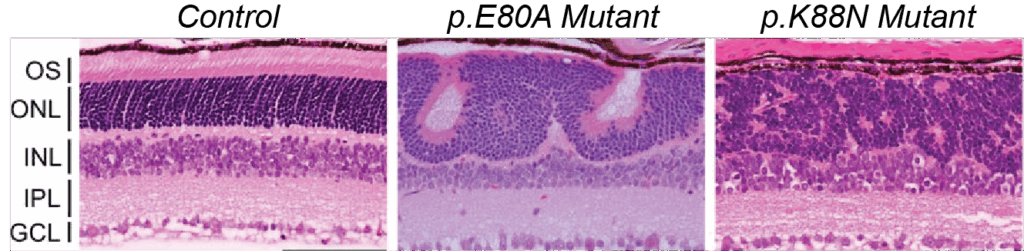

The ability of mutations to the HD region of CRX to yield such varied clinical presentations is a key area of investigation to understand inherited retinal diseases. To advance this research, scientists in the Chen Lab have developed two mouse models, carrying either the human p.E80A or p.K88N CRX HD mutations. These mutant mice successfully recapitulate key features and progressive vision loss described for human patients diagnosed with adCoRD or adLCA.

The p.E80A and p.K88N mutations yielded opposite effects on gene activation. The p.E80A mutant CRX induced premature upregulation of rod genes and downregulation of cone genes, which led to the adCoRD-like phenotype. In contrast, the p.K88N mutant CRX failed to activate both rod and cone genes, as it improperly bound to non-photoreceptor genes, which completely compromised photoreceptor differentiation. This resulted in an LCA-like phenotype.